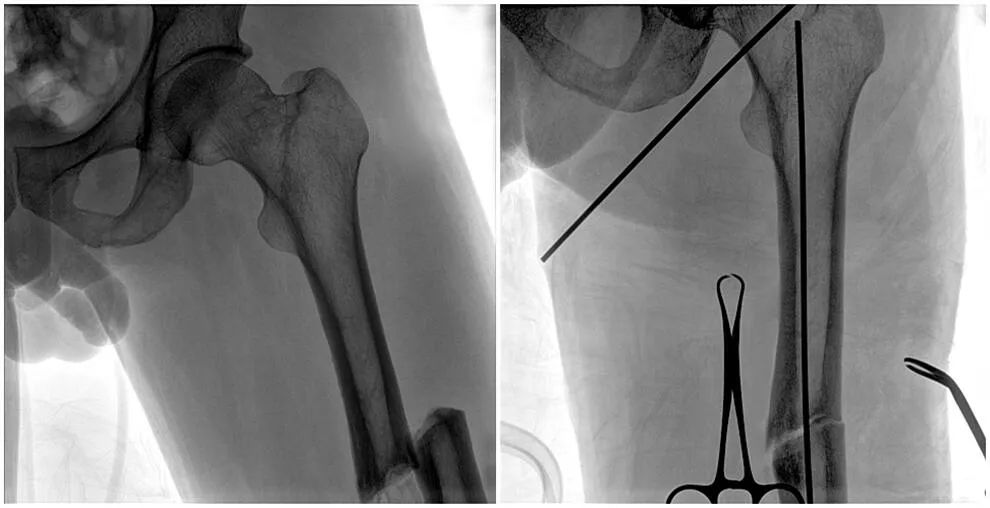

C形臂輔助手術(shù)過程

術(shù)中使用普愛醫(yī)療大平板一體式C形臂進行透視,判斷骨折情況及克氏針、髓內(nèi)釘?shù)冉饘僦踩胛锏奈恢茫M行調(diào)整。C形臂準確的術(shù)中定位,大大縮短了手術(shù)的時間,減輕了患者的痛苦,輔助手術(shù)順利完成。

在進行髓內(nèi)釘內(nèi)固定術(shù)時,醫(yī)生需要同時觀察到入釘點和骨折部位的情況,普愛醫(yī)療大平板一體式C形臂采用30CM×30CM的平板探測器,能夠呈現(xiàn)更廣闊的成像面積,滿足大部分長骨髓內(nèi)釘內(nèi)固定術(shù)的攝片需求。

術(shù)中定位準確、出血量少,術(shù)后影像顯示股骨移位糾正,恢復(fù)良好力線,手術(shù)效果良好。